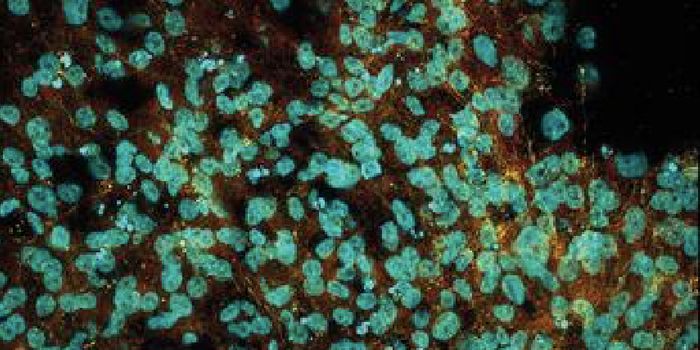

SEP 05, 2024Cell & Molecular BiologyCorynebacterium matruchotii ia a common bacterium that lives in human dental plaque; a colony is seen in this image by S ...